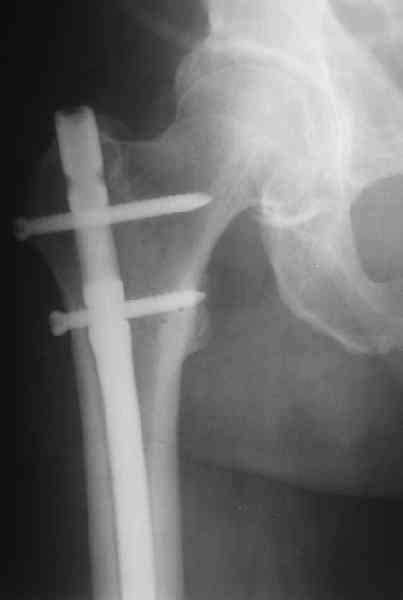

> Мужчина 60 лет, оперирован 2 месяца назад...

... Наверно, надо удалить эту пластинку и сделать реостеосинтез.

Несомненно!

> Хочется гвоздем. Или лучше не гвоздем?

Я бы предпочел реостеосинтез "не гвоздем". Хотя в свежем случае это был бы штифт...

Есть подозрение, что мыщелки отрепонированы между собой неидеально, как-будто наружный завален кзади (угол открыт кпереди). Надо удалять все железо, репонировать открыто суставные поверхности и... Я бы выбрал LCP DF (LISS) на 9 отверстий (3-5 отверстий в зоне метафизарного перелома оставить

пустыми)...

Укорочение около 2 см. Движения в колене - 45

градусов.

Как быть с укорочением?... Надо ли что-то одномоментно делать по поводу контрактуры колена?